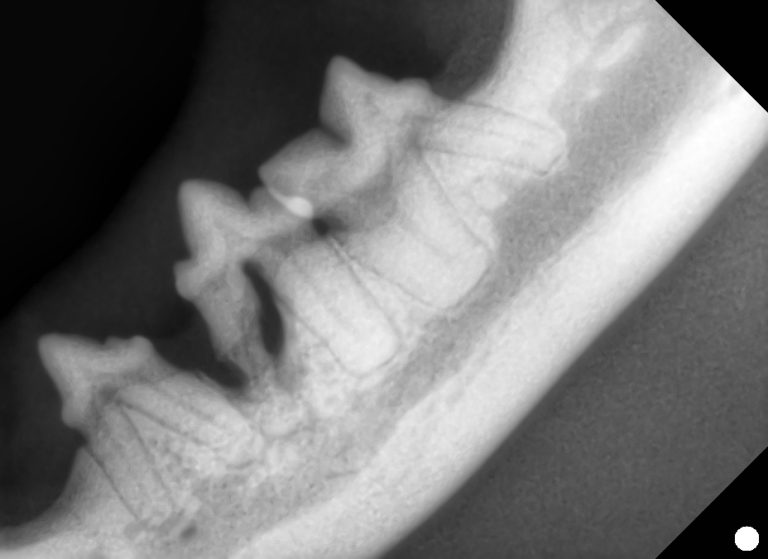

下図の通り、リンパ球由来の悪性腫瘍とされています。